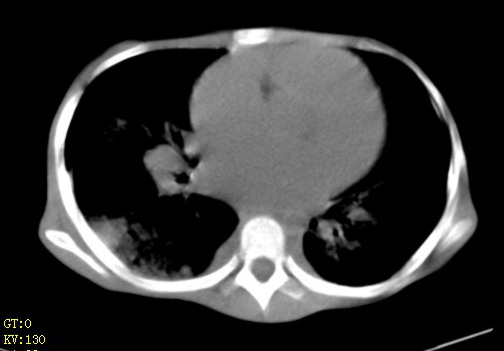

女,12岁,气促、咳嗽2天,3个月前查胸片示:两肺感染,急诊入院查ct,血常规等未检查。

先心(室缺?)、左室大,心功能不全;肺部感染

1、左心房、左心室增大,考虑左心衰, 2、肺水肿合并感染 3、双侧胸腔积液

双肺中下野不规则片絮状阴影,中外带明显,双侧胸腔少量积液,心影增大,心腔密度减低,隆突下及左侧气管旁见钙化淋巴结影,考虑双肺感染、心衰;建议结合临床除外h1n1并急性心衰,先心不能排除。

两肺多发片絮状模糊影,以下肺外带居多,内见支气管气像,纵膈窗未减影,两侧胸腔积液,心影增大,结合心超,支持重症肺炎,非常时期,甲型h1n1流感不排除。